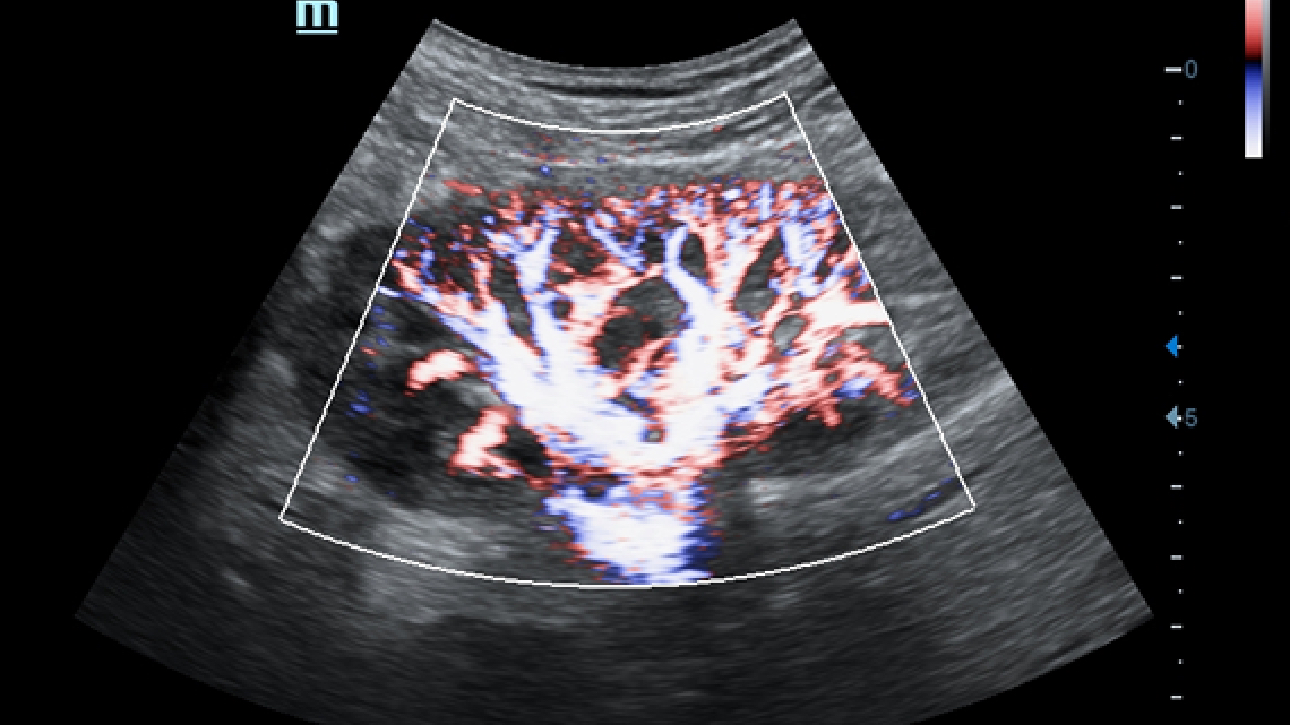

X-Insight, daha geli?mi? g?rĂŒntĂŒler elde etmek i?in kapsaml? bir ??zĂŒmdĂŒr.

Mindrayâin yeni ??zĂŒmĂŒ, geli?en en yeni ultrason teknolojileri ile birlikte, mĂŒ?terilerin g?rĂŒ?lerini klinik gerekliliklerle tam anlam?yla birle?tiren bir ??zĂŒmdĂŒr. Taptaze bir ruhla, gelece?e odaklanarak ve s?n?rs?zl???n pe?inde ko?arak, artan ?l?eklenebilirlikte sĂŒrekli olarak geli?en bir ??zĂŒmdĂŒr.

?ok y?nlĂŒ bir partner olarak, X-Insight'l? DC-60 Exp, her y?nĂŒyle gĂŒnlĂŒk klinik uygulamay? kolayl?kla ve belirsizlik olmadan y?netmenize yard?mc? olacak kapsaml? bir ??zĂŒm sunar.

MĂŒ?teri gereksinimlerine y?nelik g?rĂŒ?ler temelinde, X-Insight'l? DC-60 Exp, eXpress Clarity, eXceptional Intelligence ve eXceeding Experience ile gĂŒ?lendirilerek, hassas g?rĂŒntĂŒlemeyle yĂŒksek verimlilik sa?layacak ?ekilde tasarlanm??t?r.